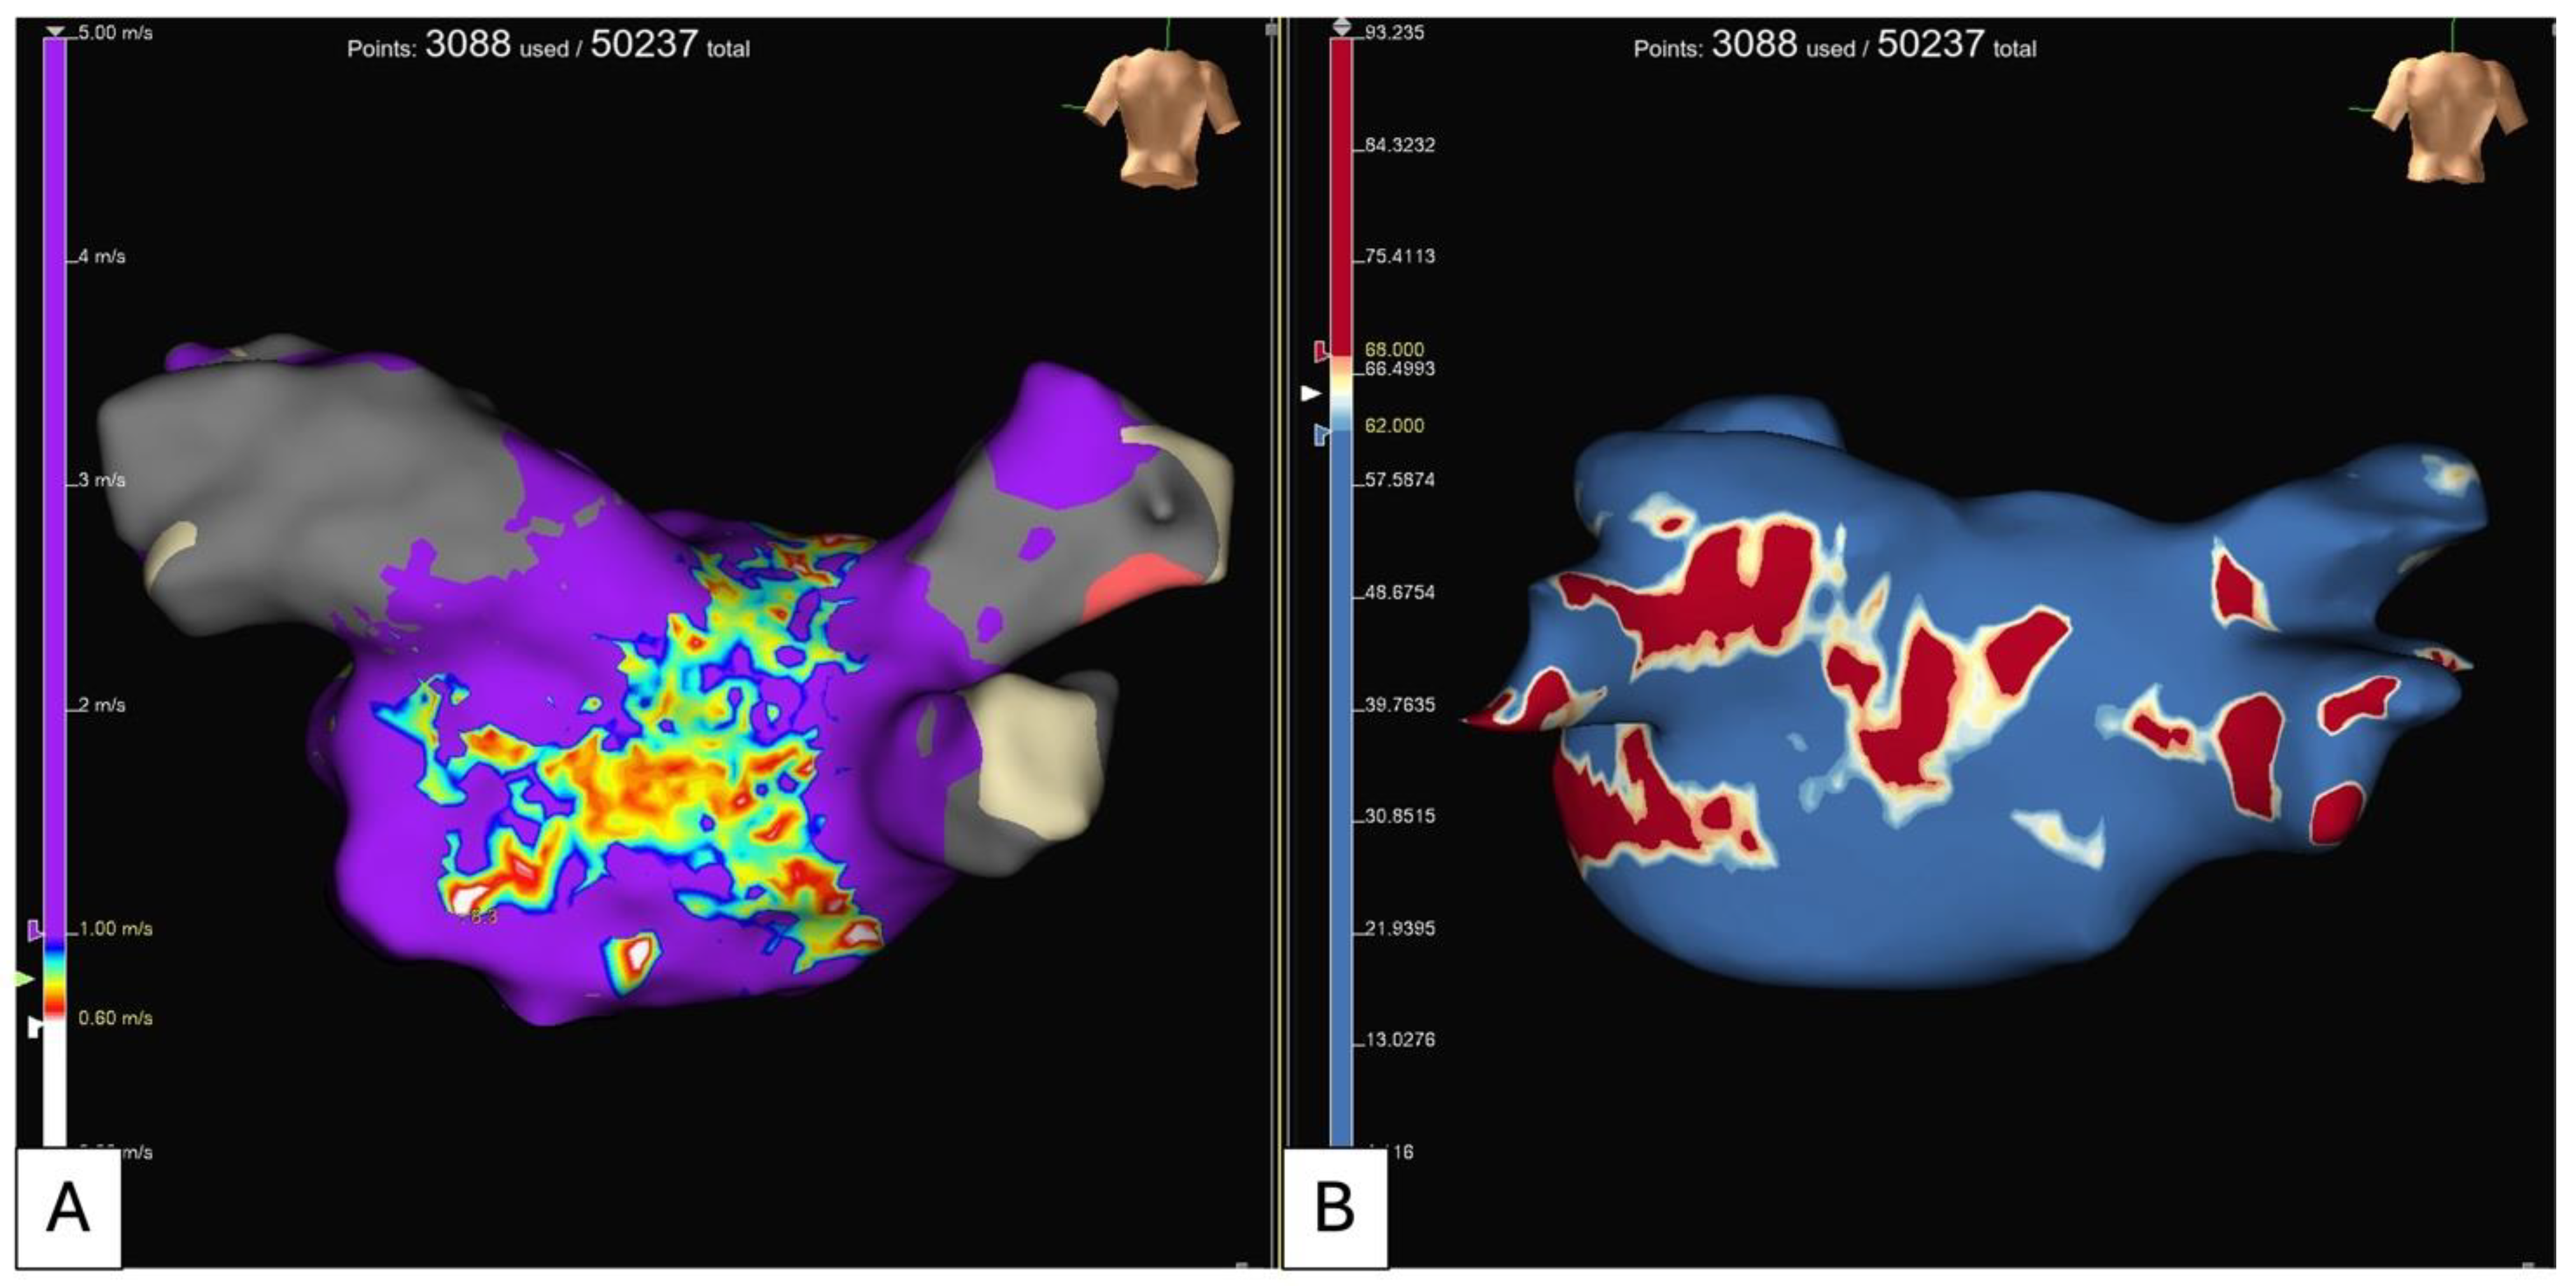

5.2. Electroanatomical Substrate Modification (Low Voltage and Complex Fractionated Electrograms Ablation)

- Rolf, S.; Kircher, S.; Arya, A.; Eitel, C.; Sommer, P.; Richter, S.; Gaspar, T.; Bollmann, A.; Altmann, D.; Piedra, C.; et al. Tailored Atrial Substrate Modification Based on Low-Voltage Areas in Catheter Ablation of Atrial Fibrillation. Circ. Arrhythmia Electrophysiol. 2014, 7, 825–833. [Google Scholar] [CrossRef] [PubMed]

- Li, K.; Xu, C.; Zhu, X.; Wang, X.; Ye, P.; Jiang, W.; Wu, S.; Xu, K.; Li, X.; Wang, Y.; et al. Multi-Centre, Prospective Randomized Comparison of Three Different Substrate Ablation Strategies for Persistent Atrial Fibrillation. Europace 2023, 25, euad090. [Google Scholar] [CrossRef]